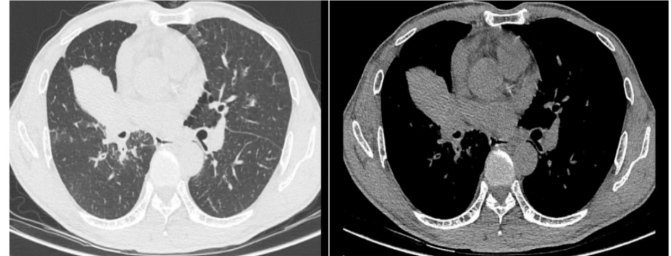

在当地医院检查后,CT报告上“不排除肺肿瘤可能性”的字样让刘叔一家陷入了焦虑。为求进一步明确诊断,刘叔来到广州中医药大学番禺医院(番禺区中医院)呼吸与危重症医学科就诊。

呼吸与危重症医学科罗胜主任接诊后,立即组织医疗团队对病情进行深入分析。结合刘叔的胸部影像学报告,医疗团队初步判断其存在“右肺门肺肿瘤、肺门淋巴结肿大”。罗胜主任指出:“病灶位置很深,紧贴着大血管,常规检查手段难以安全到达,诊断面临很大挑战。”